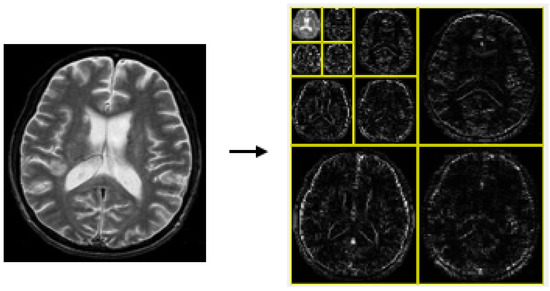

- The 2D discrete wavelet transform (DWT): Preprocessed gray matter images are decomposed into multiscale features, capturing both broad structural patterns and fine textures that may indicate early AD.

3.2. Feature Extraction via DWT